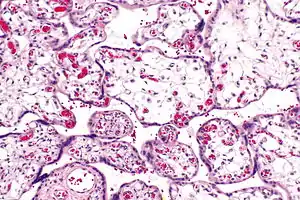

| Micrograph of villous immaturity. H&E stain. | |

Immature chorionic villi are larger and have more central blood vessels; thus, the diffusion distance for gas and nutrient exchange is larger and, therefore, placental function is impaired.